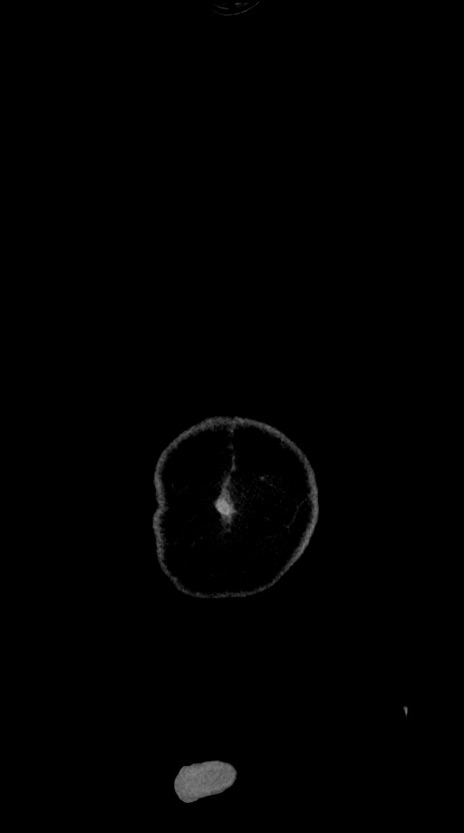

横断像

【症例】60歳代男性

【主訴】嘔吐

【現病歴】胃癌にて胃全摘後。食思不振が悪化し、夜中に嘔吐することがある。

【既往歴】胃癌、胃全摘、脾摘、胆摘後

【データ】WBC 5900、CRP 10.56